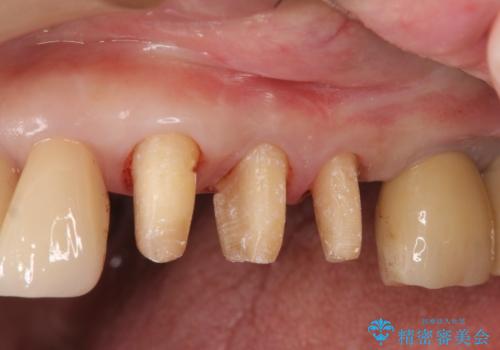

- 夜間のくいしばり、はぎしりが激しく全体的な歯周病が進行し、治療を希望され来院されました。

歯周ポケットの徹底的な除去を行なったのち、歯の揺れを抑え、過大な力がかからぬよう連結クラウン(歯周補綴)を行い強大な力に対抗します。